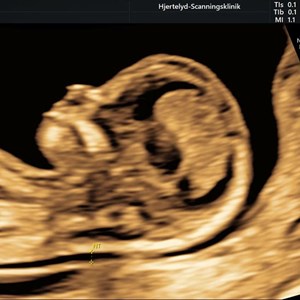

Hjertelyd - scanningsklinik for gravide

5. juli 2024

Når kvalmen virkelig har magten ! - så kan det være beroligende og glædeligt at få et kig...